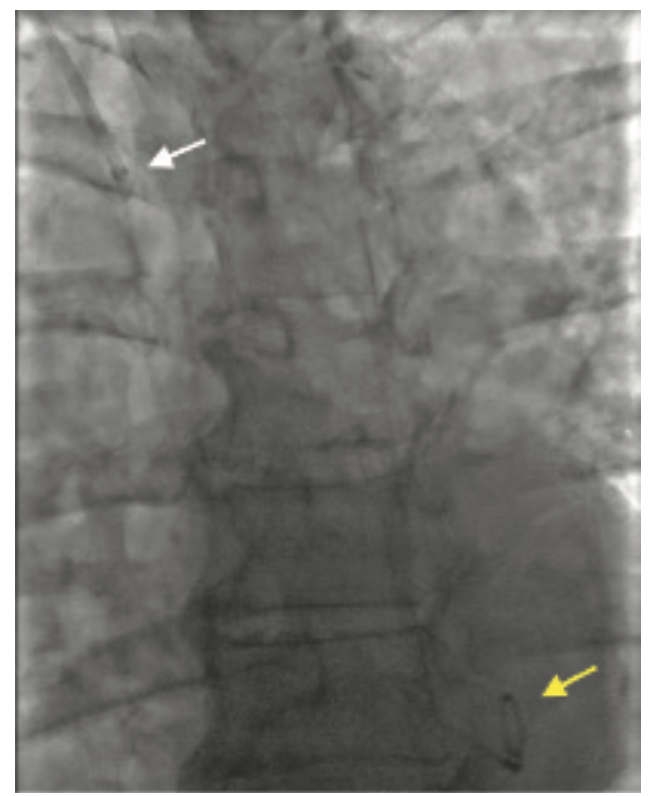

An 82-year-old female presented with New York Heart Association (NYHA) Class III dyspnea and Canadian Cardiovascular Society (CCS) Class III angina. Other comorbidities include severe cardiomyopathy with reduced ejection fraction (EF) of 25%-30%, severe functional mitral regurgitation, chronic kidney disease stage III, and severe frailty. A diagnostic coronary angiogram revealed severe multivessel disease involving the right coronary artery (RCA) and left anterior descending (LAD) artery. More importantly, the patient had a tortuous brachiocephalic artery with a 360-degree loop (Figure 1). She was evaluated by a heart team and found to be at high risk for surgery with a Society of Thoracic Surgeons (STS) score of >8%. A decision was made to perform percutaneous coronary intervention (PCI) followed by percutaneous valve repair in a staged fashion.

Access site selection was paramount in our frail, elderly female to reduce vascular complications. Despite radial access being our preferred first access, there were some concerns, given a severely tortuous brachycephalic artery. The ascending aorta was accessed with a stiff angled Glidewire (Terumo) followed by an Amplatz Super Stiff™ guidewire (Boston Scientific) in an effort to straighten the brachiocephalic loop, but with no success. We accessed the ascending aorta with a 6 French (F) 75 cm R2P™ DESTINATION SLENDER™ Guiding Sheath. Image-guided RCA PCI was completed uneventfully, despite the presence of a 360-degree right brachiocephalic loop (Figure 1A-D).